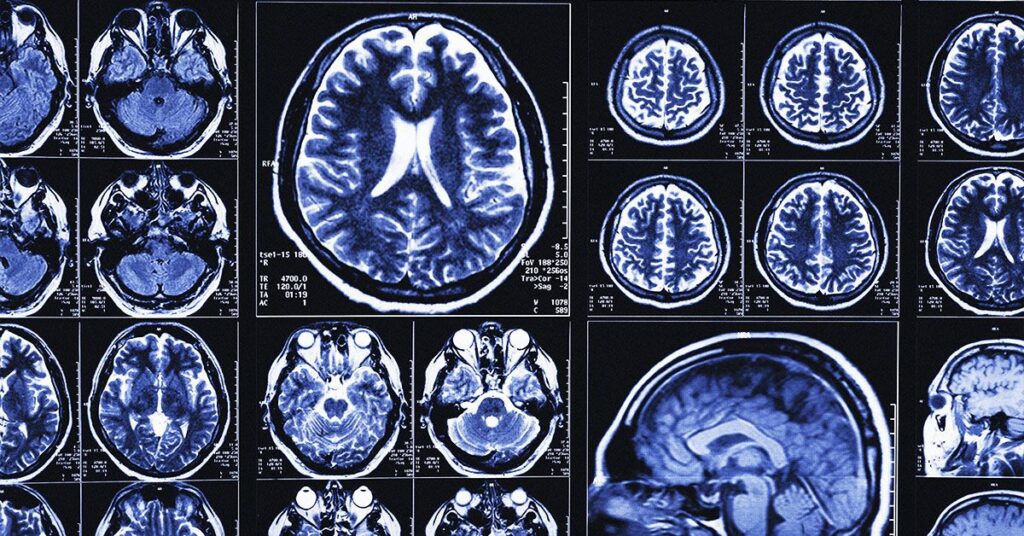

To build their AI tool, researchers used cognitive tests and MRI scan data from more than 400 people in a U.S.-based research group.

They then tested their AI tool on data from another 600 people in the U.S. research group, as well as 900 participants from memory clinics in the U.K. and Singapore.